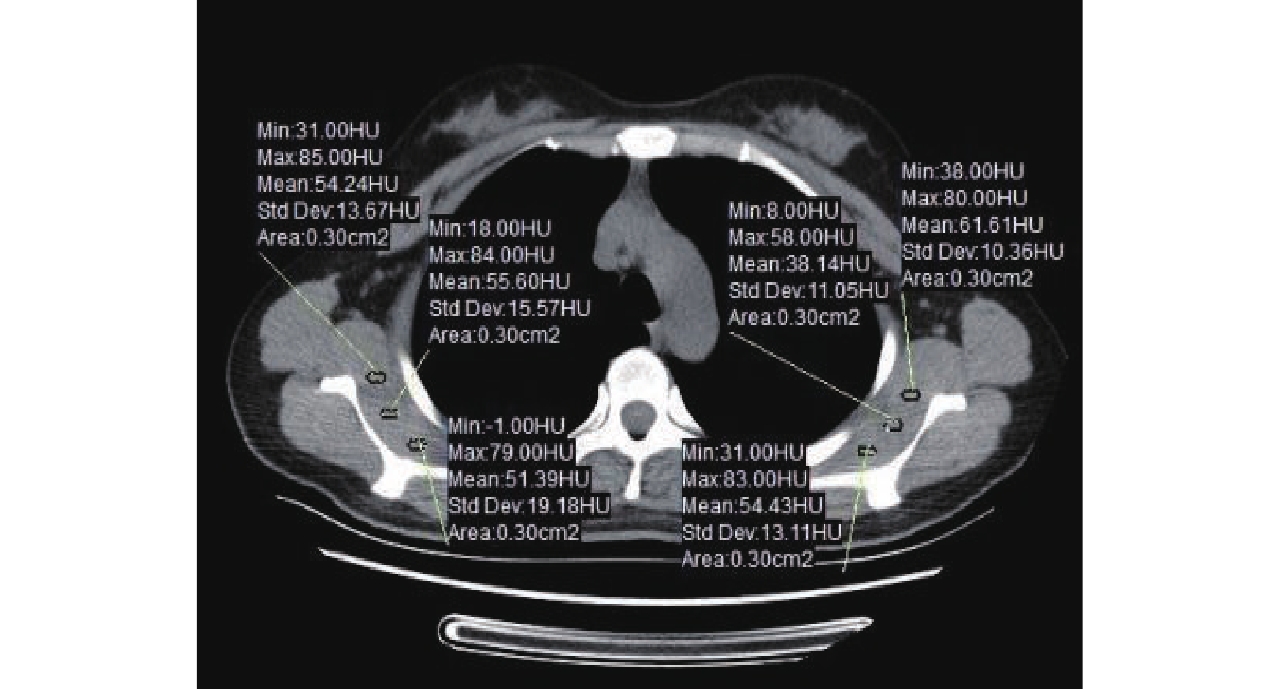

Table 4 The objective evaluation between the two groups

分组及检验 CNR SNR 低剂量组 28.83±2.95 30.62±3.10 常规剂量组 28.98±2.48 30.69±2.46 Z -0.851 -0.673 P 0.395 0.501 -